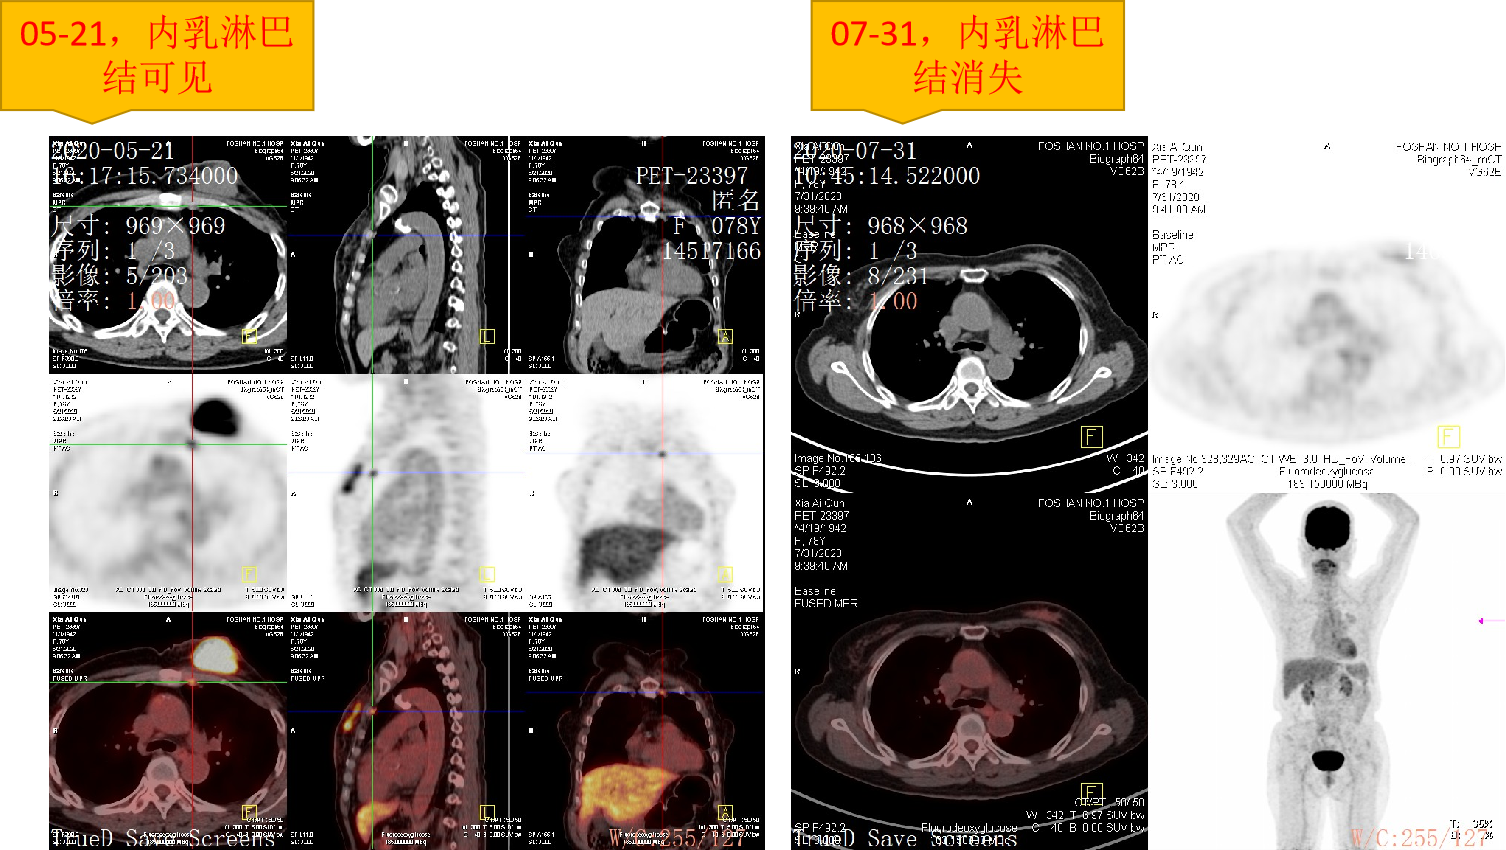

疗效评估:

PET-CT:内乳淋巴结消失。

7.png图7.疗效评估PET-CT